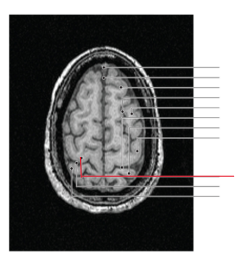

fissura longitudinalis cerebri

nucleus caudatus

putamen

globus pallidus

capsula interna (corona radiata)

capsula externa

capsula extrema

laterale ventrikels (I en II)